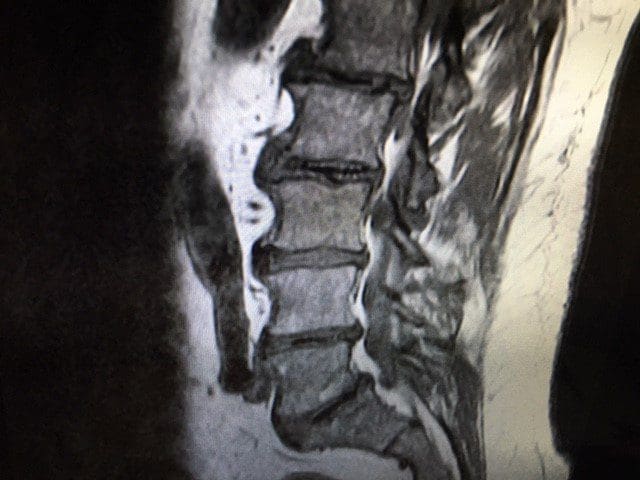

Lumbar MRI without contrast was ordered immediately with a 4 mm slice thickness and 1 mm gap in between slices on a Hitachi Oasis 1.2 Telsa machine for optimal visualization of pathology due to the clinical presentation of right L5 nerve root compression.

Lumbar MRI Imaging Results

- Significant degenerative changes throughout the lumbar spine including multi-level degenerative disc changes at all levels.

- Transverse Annular Fissures at L1-2 (17.3 mm), L2-3 (29.5 mm), L4-5 (14.3 mm) and L5-S1 (30.8 mm) and broad based disc bulging at all levels except L5-S1. The fissures at L2-3 and L5-S1 both have radial components extends through to the vertebral endplate.

- Facet osteoarthritic changes and facet effusions at all levels.

- Grade II spondylitic spondylolisthesis is confirmed at L5-S1 with severe narrowing of the right neural foramen compressing the right exiting L5 nerve root.

- Degenerative retrolisthesis at L1-2.

- Modic Type II changes at L2 inferior endplate, L3 superior endplate, L4 inferior endplate and L5 inferior endplate.2

- There is a 18.9 mm wide Schmorl’s node at the superior endplate of L3.

- There is a 5.7 mm wide focal protrusion type disc herniation at L4-5 which impinges on the thecal sac.

T2 sagittal Lumbar Spine MRI: Note the Modic Type II changes and the L2-3 Schmorls node.

T1 Sagittal Annular fissures at multiple levels and spondylolisthesis at L5S1